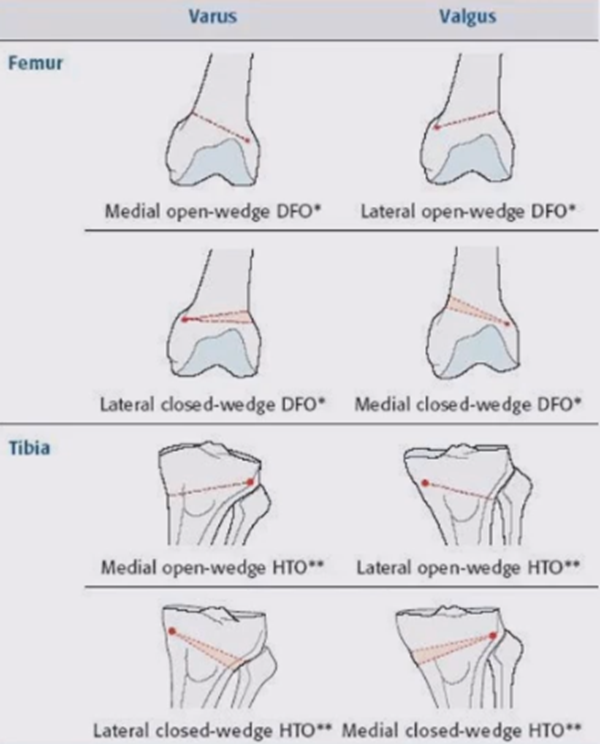

膝关节周围截骨术通过改善膝关节负重轴线以达到矫正畸形、稳定膝关节和解除疼痛三方面目的,常规的膝关节周围截骨术主要包括胫骨高位截骨术(HTO)和股骨远端截骨术(DFO)等。DFO采用内侧或外侧股骨截骨,可以有效纠正膝关节力线。

①股骨髁上畸形(内、外翻)伴/不伴单间室骨关节炎;②儿麻后遗症;③骨折畸形愈合等。

①单间室OA合并对侧间室;②半月板撕裂或缺失;③3度以上的软骨磨损;④多间室骨关节炎;⑤炎症性关节炎,如类风湿性关节炎、强直性脊柱炎等。